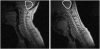

Rapid deformation of brain tissue in response to head impact or acceleration can lead to numerous pathological changes, both immediate and delayed. Modeling and simulation hold promise for illuminating the mechanisms of traumatic brain injury (TBI) and for developing preventive devices and strategies. However, mathematical models have predictive value only if they satisfy two conditions. First, they must capture the biomechanics of the brain as both a material and a structure, including the mechanics of brain tissue and its interactions with the skull. Second, they must be validated by direct comparison with experimental data. Emerging imaging technologies and recent imaging studies provide important data for these purposes. This review describes these techniques and data, with an emphasis on magnetic resonance imaging approaches. In combination, these imaging tools promise to extend our understanding of brain biomechanics and improve our ability to study TBI in silico.